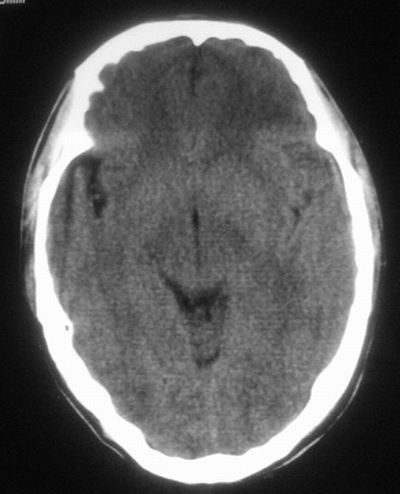

治疗三天后复查ct片示:

治疗三天后复查ct:除左侧额顶叶血肿外。左侧额叶另见片状低密度灶,密度不均匀,境界不清;考虑脑梗塞。

建议:必要时行进一步检查排除烟雾病。